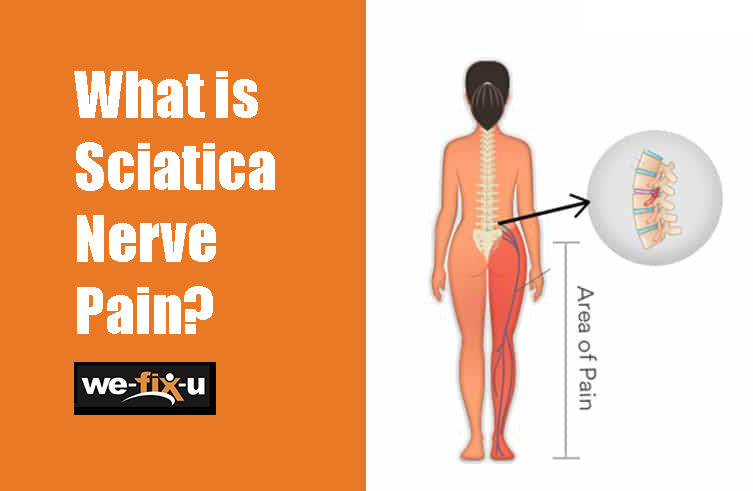

Download Sciatic nerve pain pictures